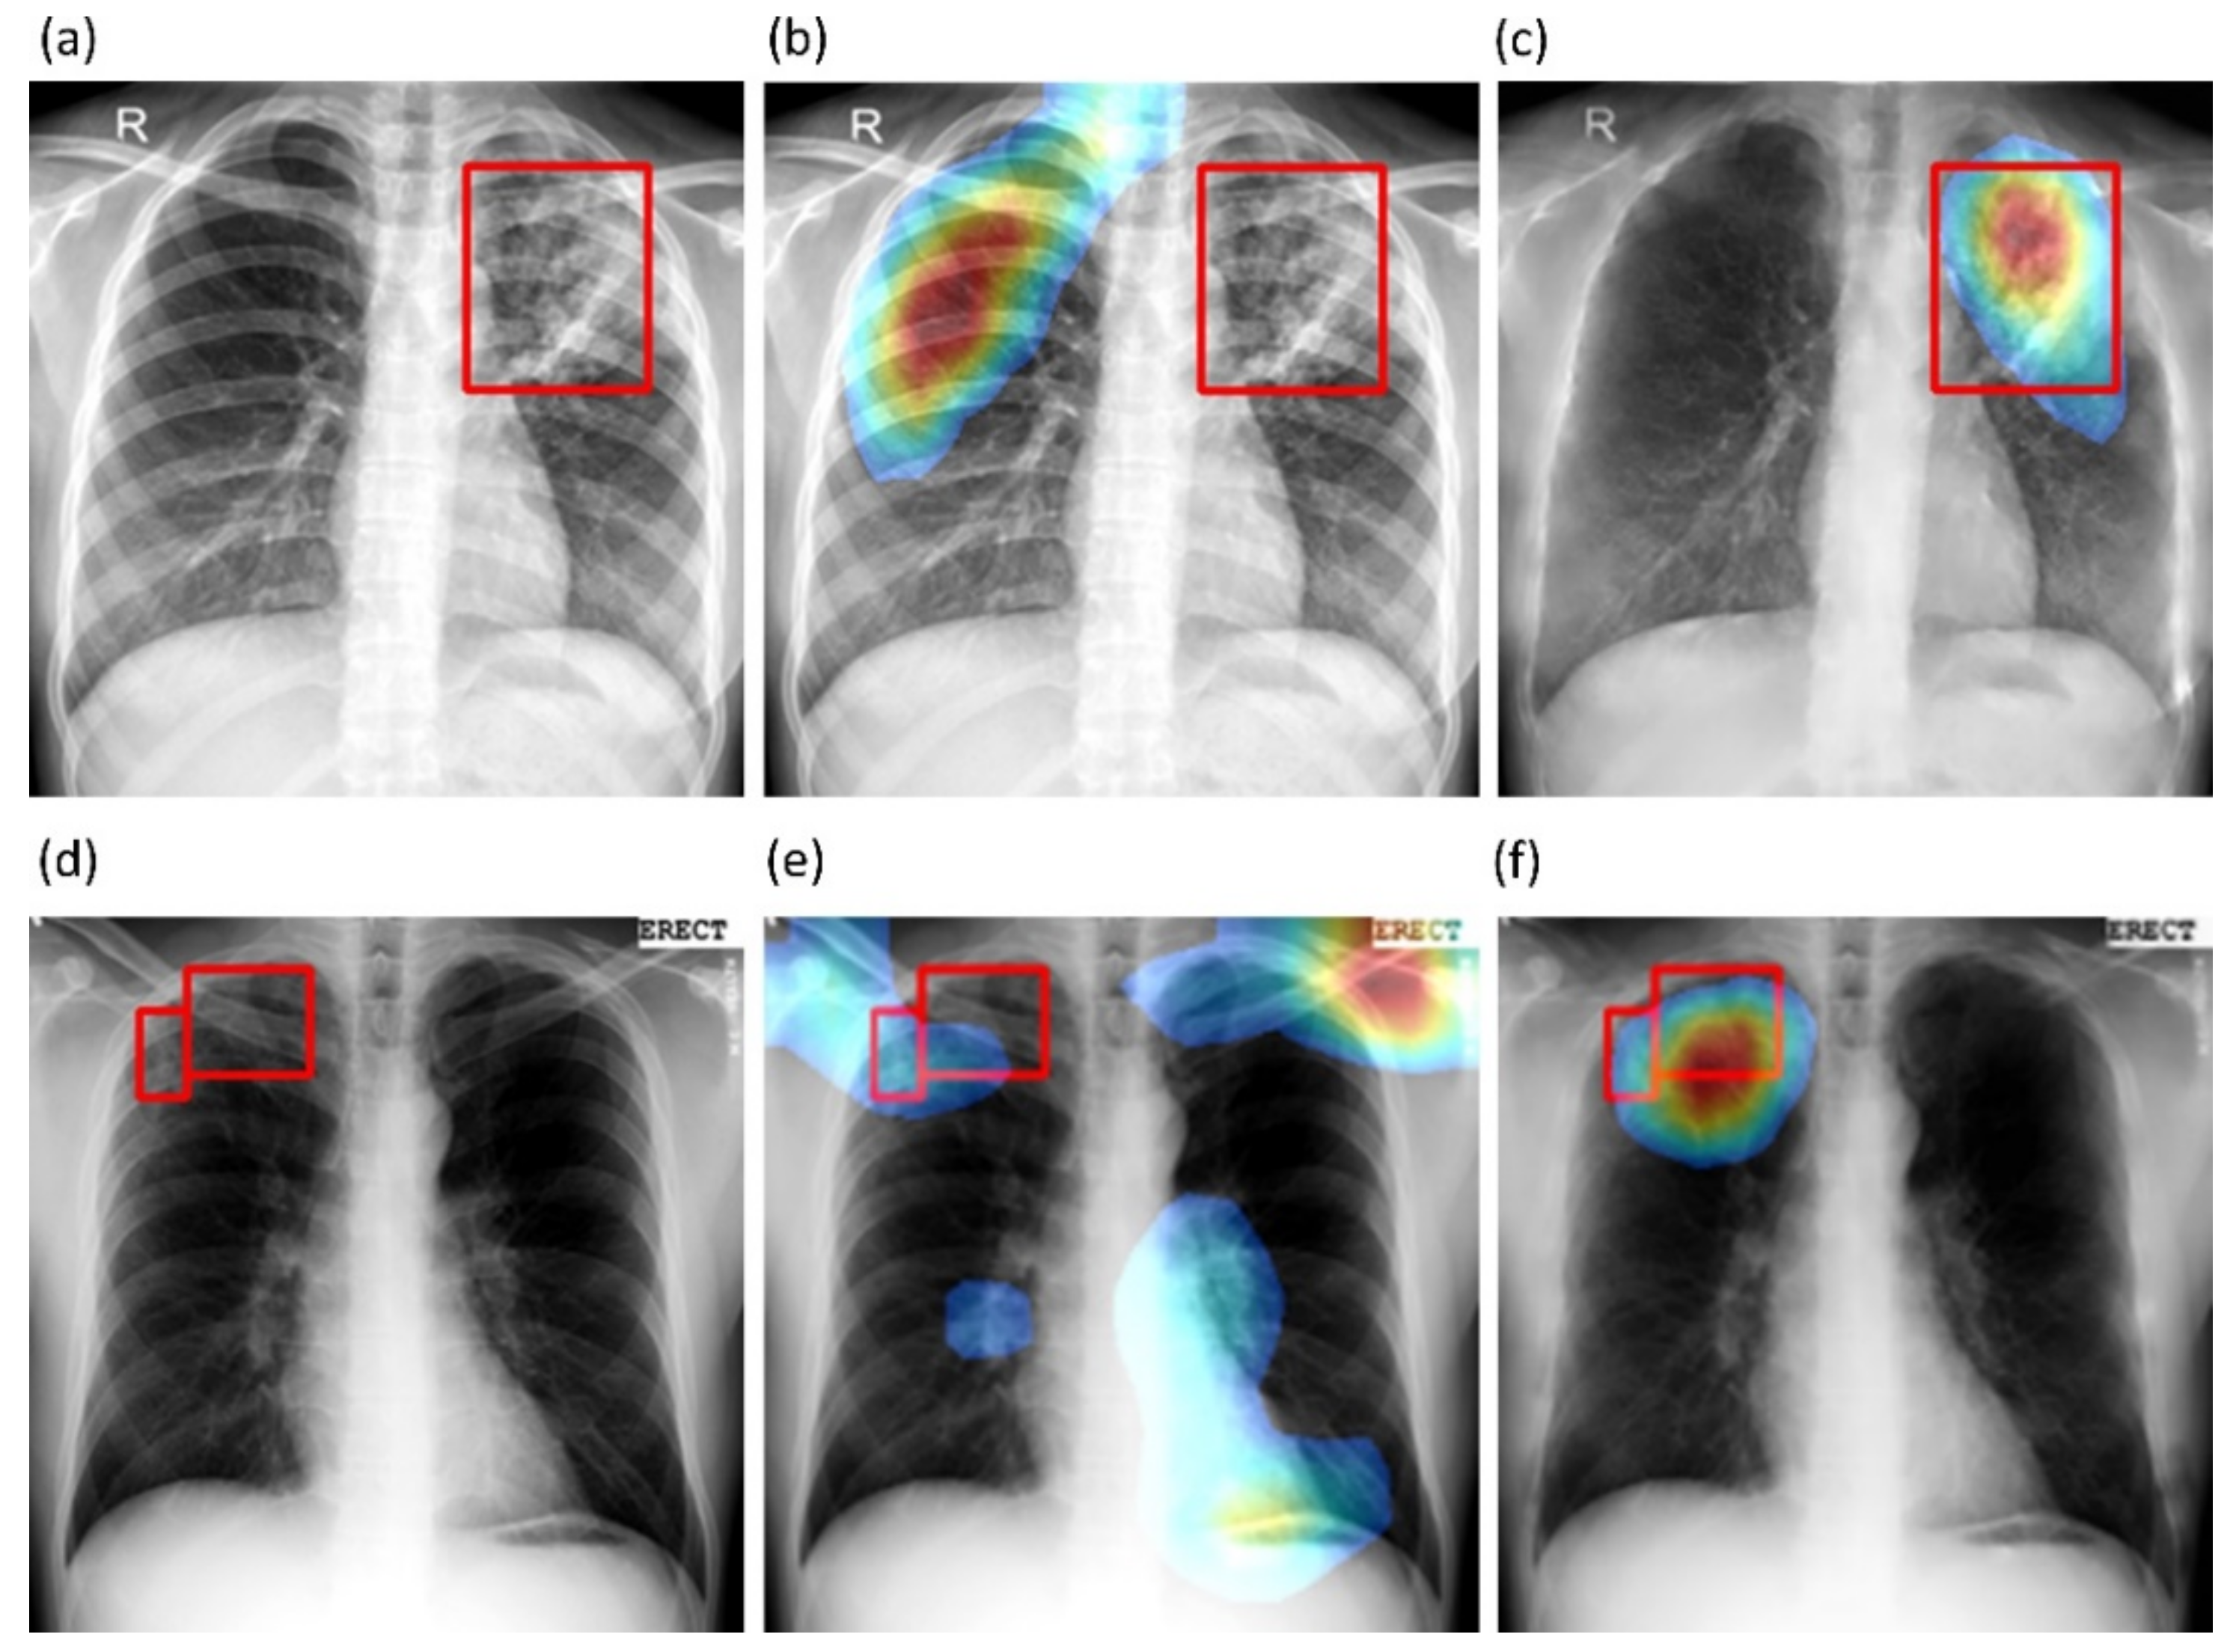

We also used CRMs to interpret the predictions of the best-performing baseline and bone-suppressed models using the Shenzhen and Montgomery TB CXR collections to localize TB-consistent findings. Figure 10a,d show instances of original CXRs, respectively, from the Shenzhen and Montgomery TB CXR collections. The expert ground truth annotations are shown with red bounding boxes. Figure 10b,e show how the best-performing baseline models interpret their prediction toward localizing TB-consistent ROI. Figure 10c,f show the TB-consistent ROI localized by the best-performing bone-suppressed models. It is observed that the bone-suppressed models demonstrated superior TB-consistent ROI localization, compared to the baseline models. From Figure 10b,e, it is observed that the baseline models are learning the surrounding context but not meaningful features. The TB-consistent ROI localization achieved by the bone-suppressed models conformed to the expert knowledge of the problem, as observed from Figure 10c,f, and showed that it learned meaningful, salient feature representations.

Figure 10. CRM-based TB-consistent ROI localization achieved by the best-performing baseline and bone-suppressed model, respectively, using a sample CXR from the Shenzhen and Montgomery TB CXR collection. (a) a CXR instance from the Shenzhen TB CXR collection with expert ground truth annotations (shown with red bounding boxes); (b) TB-consistent ROI localization achieved by the best-performing baseline model using the Shenzhen CXR instance; (c) TB-consistent ROI localization achieved by the best-performing bone-suppressed model using the Shenzhen CXR instance; (d) a CXR instance from the Montgomery TB CXR collection with expert ground truth annotations (shown with red bounding boxes); (e) TB-consistent ROI localization achieved by the best-performing baseline model using the Montgomery CXR instance, and (f) TB-consistent ROI localization achieved by the best-performing bone-suppressed model using the Montgomery CXR instance.